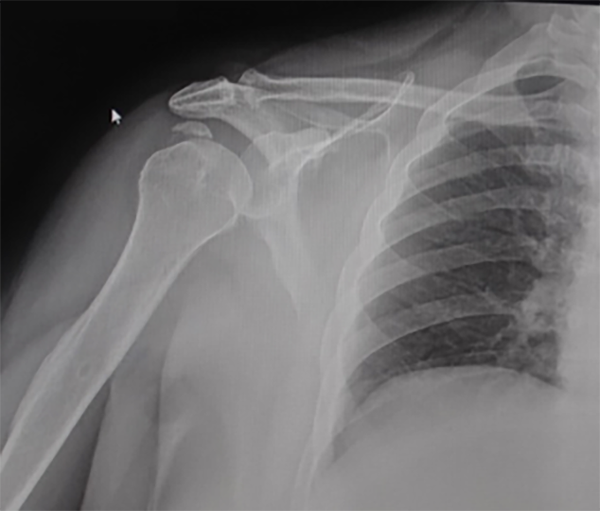

El hombro fue reducido bajo sedación en el quirófano, se colocó cabestrillo, se tomó radiografía de control (fig. 2) y fue dada de alta con medicación.

Figura 2: Radiografía AP (no verdadera) de control posreducción.